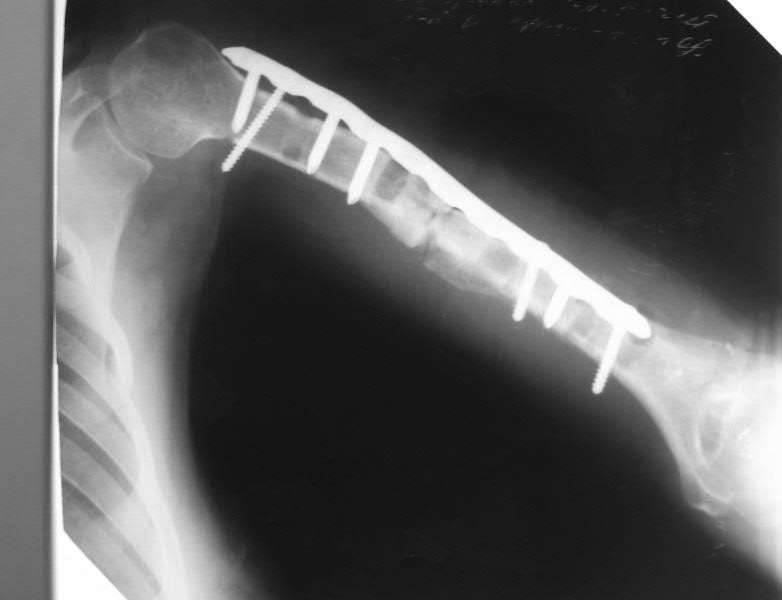

дефект-диастаз левой плечевой кости

Два года назад - перелом плеча.

Последовательно ставили три пластины. На все - отторжение металла.

Сейчас - дефект-диастаз+укорочение. Суммарный дефект около 6 см. Дырки от винтов. Инфекции нет.

В данном случае отсутствуют симптомы металлоза, потому что не видны обьективные данные, такие, как наличие боли, образование локальных некротических участков, формация кист и псевдотуморов. Но явно видны следы неудачной фиксации и слабой хирургической техники.